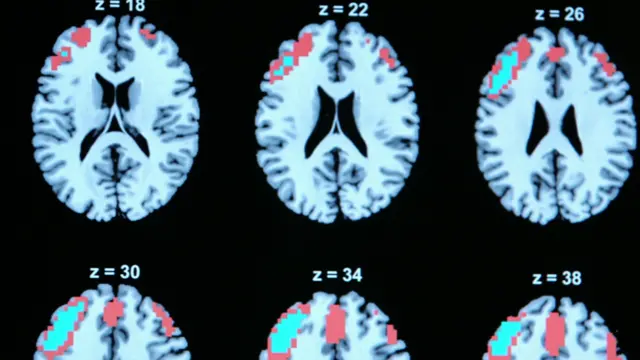

"No sabemos exactamente por qué la terapia funciona en niños con autismo; lo que creemos es que probablemente regula los circuitos del cerebro que están desarticulados por culpa del autismo", explicó Kellner.

"La TEC deja una herida traumática en el cerebro. La corriente eléctrica viaja no sólo a través del lóbulo frontal, donde está la inteligencia y la creatividad, sino también en el lóbulo temporal, donde se encuentra la memoria", le dice a la BBC el siquiatra Peter Breggin, quien se opone totalmente al uso de esta terapia.